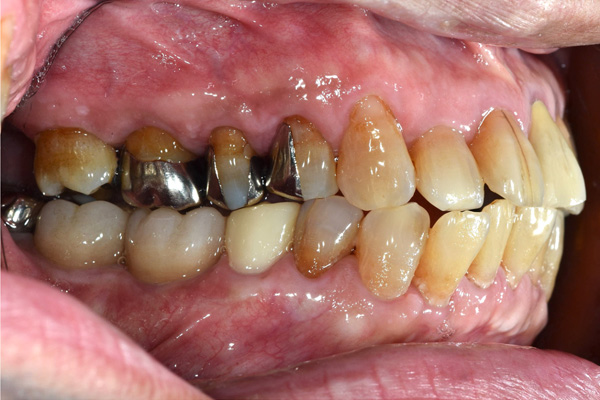

| 主訴 | 右下の歯がないのでインプラントをして欲しい |

| 治療期間 | 約6ヶ月 |

| 費用 | 600,000円 |

| 治療内容 | インプラント、骨造成、結合組織移植、セラミック修復 |

| 治療に伴うリスク | インプラント周囲炎 セラミックの破折、脱離 |